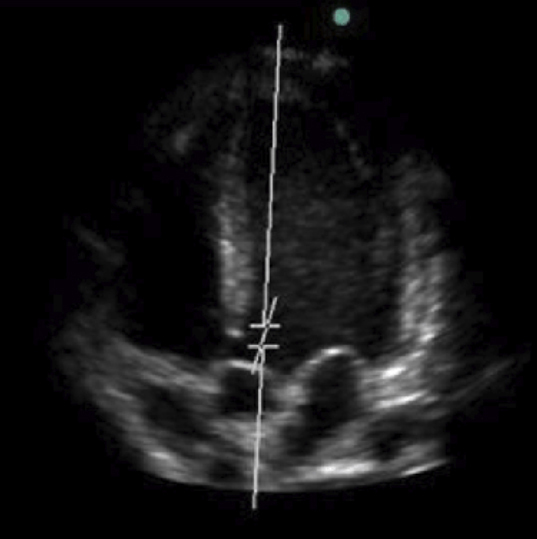

Figure 2 (Elon Zerah, La Revue du Praticien)

On visualise la valve tricuspide entre l’oreillette droite et le ventriculaire droit, la valve mitrale entre l’oreillette gauche et le ventricule gauche, ainsi que la valve aortique dans la chambre de chasse ventriculaire gauche. La valve pulmonaire ne peut pas être visualisée sur cette coupe :

Il faut maîtriser les principales coupes à l’ETT pour identifier les différentes structures anatomiques intra-cardiaques : apicales 2, 3, 4 et 5 cavités, para-sternale grand axe et sous-costale.